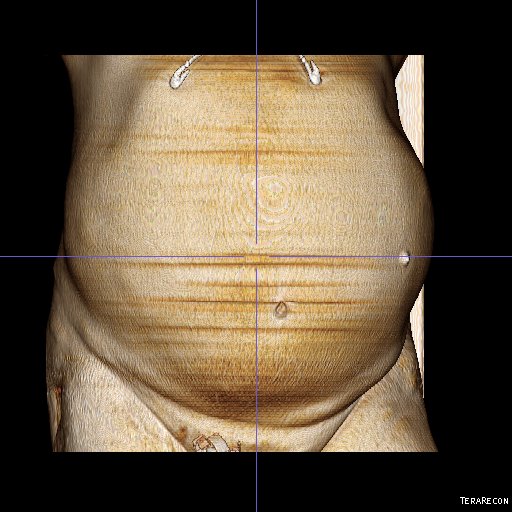

This patient presents with lifestyle limiting claudication and an absent right femoral pulse. ABI is moderately reduced on the right to 0.57, and he had no rest pain. CTA at our clinic revealed an occluded EIA bracketed by severely calcified and nearly occlusive plaque of the common iliac artery (CIA) and common femoral artery (CFA).

The patient was operated on in a hybrid endovascular OR suite. A right groin incision was made to expose the common femoral artery for endarterectomy and left common femoral access was achieved for angiographic access, but also to place a wire across the occlusion into the common femoral artery.

All actions on the external iliac artery plaque are done with an up-and-over wire, allowing for swift action in the instance that arterial perforation or rupture occur. This event is exceedingly rare when the operation is well planned. With this kind of access, an occlusive balloon or repairing stent graft can be rapidly delivered.

The common femoral endarterectomy is done from its distal most point and the Vollmer ring is used to mobilize the plaque. A Moll Ring Cutter (LeMaitre Vascular) is then used to cut the plaque.

The plaque is extracted and re-establishes patency of the EIA.

The plaque end point is typically treated with a stent -in this case, the common iliac plaque was also treated.